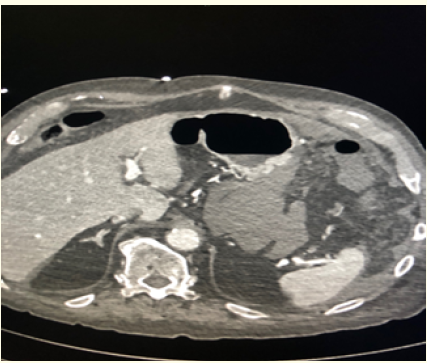

Cardiac Hydatid Cyst of the Interventricular Septum Complicated by 03rd Degree Atrioventricular Block in a Pregnant Woman: A Case Report

Lakehal Redha, Khacha Khaled, Babouri Abdelrahman, Bendjaballah Soumaya, Aziza Baya and Bouzid Abdelmalek. 5(10): 46-50.